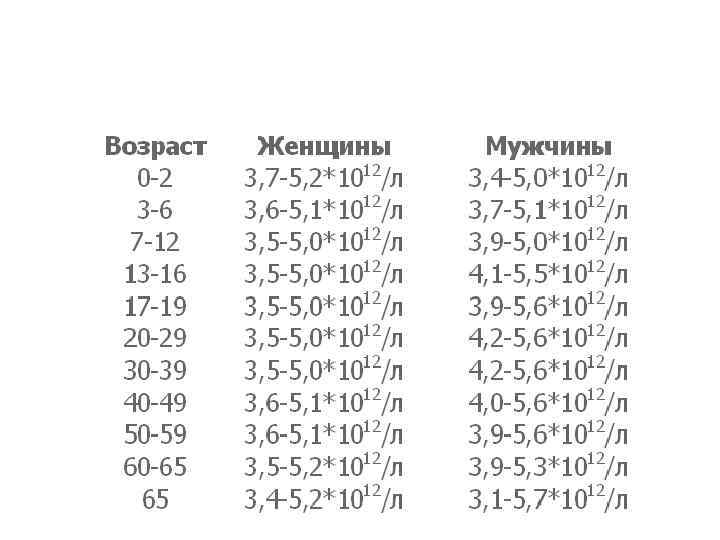

Количество эритроцитов • В норме число эритроцитов у мужчин равно 4 — 5 1012/л, • или 4 000 - 5 000 в 1 мкл крови. • У женщин количество эритроцитов меньше и, как правило, не превышает 4, 5 1012/л. • При беременности число их может достигать 3, 5 1012/л и даже 3, 2 1012/л.

Количество эритроцитов • В норме число эритроцитов у мужчин равно 4 — 5 1012/л, • или 4 000 - 5 000 в 1 мкл крови. • У женщин количество эритроцитов меньше и, как правило, не превышает 4, 5 1012/л. • При беременности число их может достигать 3, 5 1012/л и даже 3, 2 1012/л.